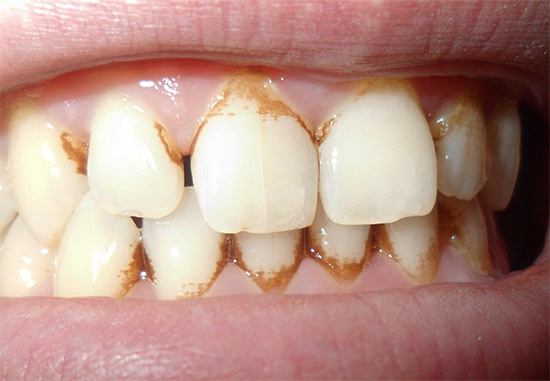

- Violazione dell'igiene orale.Un costante accumulo di placca nella regione cervicale del dente o una corona di scarsa qualità senza un'igiene adeguata e regolare spesso porta alla gomma e alla carie subgengivale a causa di fattori cariogenici nella dissoluzione dello smalto dei denti e del cemento radicolare.

- Rimozione di depositi dentali sopra e sottogengivali: pulizia della placca e della pietra da tutte le superfici dei denti. Poiché la malattia gengivale è spesso innescata da tartaro e placca, al fine di effettuare una diagnosi corretta, è necessario pulire a fondo l'area di ispezione dai depositi. Per questo vengono utilizzati metodi manuali (scaler, scalpelli, curette, ecc.), Punte e dispositivi ad ultrasuoni per la pulizia ad ultrasuoni dei denti (punta per lo scaler dell'unità dentale, Piezon-master, ecc.), Così come il trattamento dentale con Air Flow.